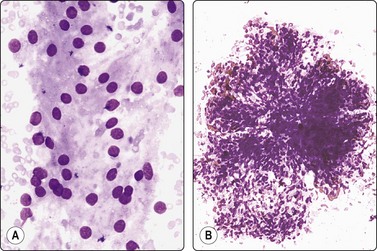

Metanephric adenoma99-102

Metanephric (embryonal) adenoma is a rare benign renal tumor arising from metanephric blastema, most often seen in middle-aged women. A few cases with cytology have been reported. Smears are relatively cellular of monomorphous cells with small oval overlapping nuclei, bland chromatin and scanty cytoplasm. The cells are arranged in micropapillary or trabecular clusters and rosette-like, small tubular or microfollicular groups. The cell groups are associated with scanty stromal, basement membrane-like material sometimes forming a thin central core in small rounded clusters (Fig. 12.25). Figure 12.26 is of similar FNB findings from a solitary, well-circumscribed renal lesion in a 70-year-old woman, radiologically thought to be a cyst. It had been present for 15 years, showing no change. The cytology in conjunction with the clinical/radiological findings was consistent with metanephric adenoma, and surgery was not performed.

image image

Fig.12.25 Metanephric adenoma

(A) Single and clustered cells forming small trabecular and follicular groups, some with hyaline stromal material in the center (Pap; HP); (B) Tissue section, immunostaining for WT1 (IP)

(Courtesy Dr. L. Francis, Brisbane).

Fig.12.26 Metanephric adenoma

(A) Cellular smear of clusters of small cells with uniform oval bland nuclei and scanty cytoplasm, some cells forming small round tubular groups; (B) The same smear contained tissue fragments almost like a cell block, showing microarchitectural features of trabecular or tubular groups separated by stroma (A, DQ, HP; B, IP).

The main differential diagnoses are well-differentiated Wilms’ tumor and papillary RCC. Patel et al.100 propose a battery of immune markers (WT1, CD57, CD56, AMACR, CK7) to help in this distinction.